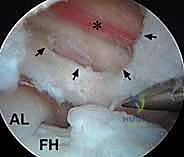

1. النوع الداخلي (Internal Snapping Hip)

هذا هو النوع الأكثر شيوعًا، وغالبًا ما يكون السبب وراء شعور المريض بطقطقة عميقة في مقدمة الورك أو منطقة الفخذ (Groin). ينجم هذا النوع عن انزلاق وتر العضلة الحرقفية القطنية (Iliopsoas tendon) ذهابًا وإيابًا فوق هياكل عظمية بارزة، مثل البروز العاني الحرقفي أو رأس عظم الفخذ، أثناء حركة الورك من وضعية الثني إلى وضعية التمدد.

مع تكرار هذا الاحتكاك، يلتهب الوتر نفسه، أو يلتهب الجراب الزلالي الحرقفي القطني (Iliopsoas Bursa) - وهو كيس صغير مملوء بالسائل يقع بين الوتر والعظم لتقليل الاحتكاك - مما يسبب ألمًا حادًا يعيق الحركة.